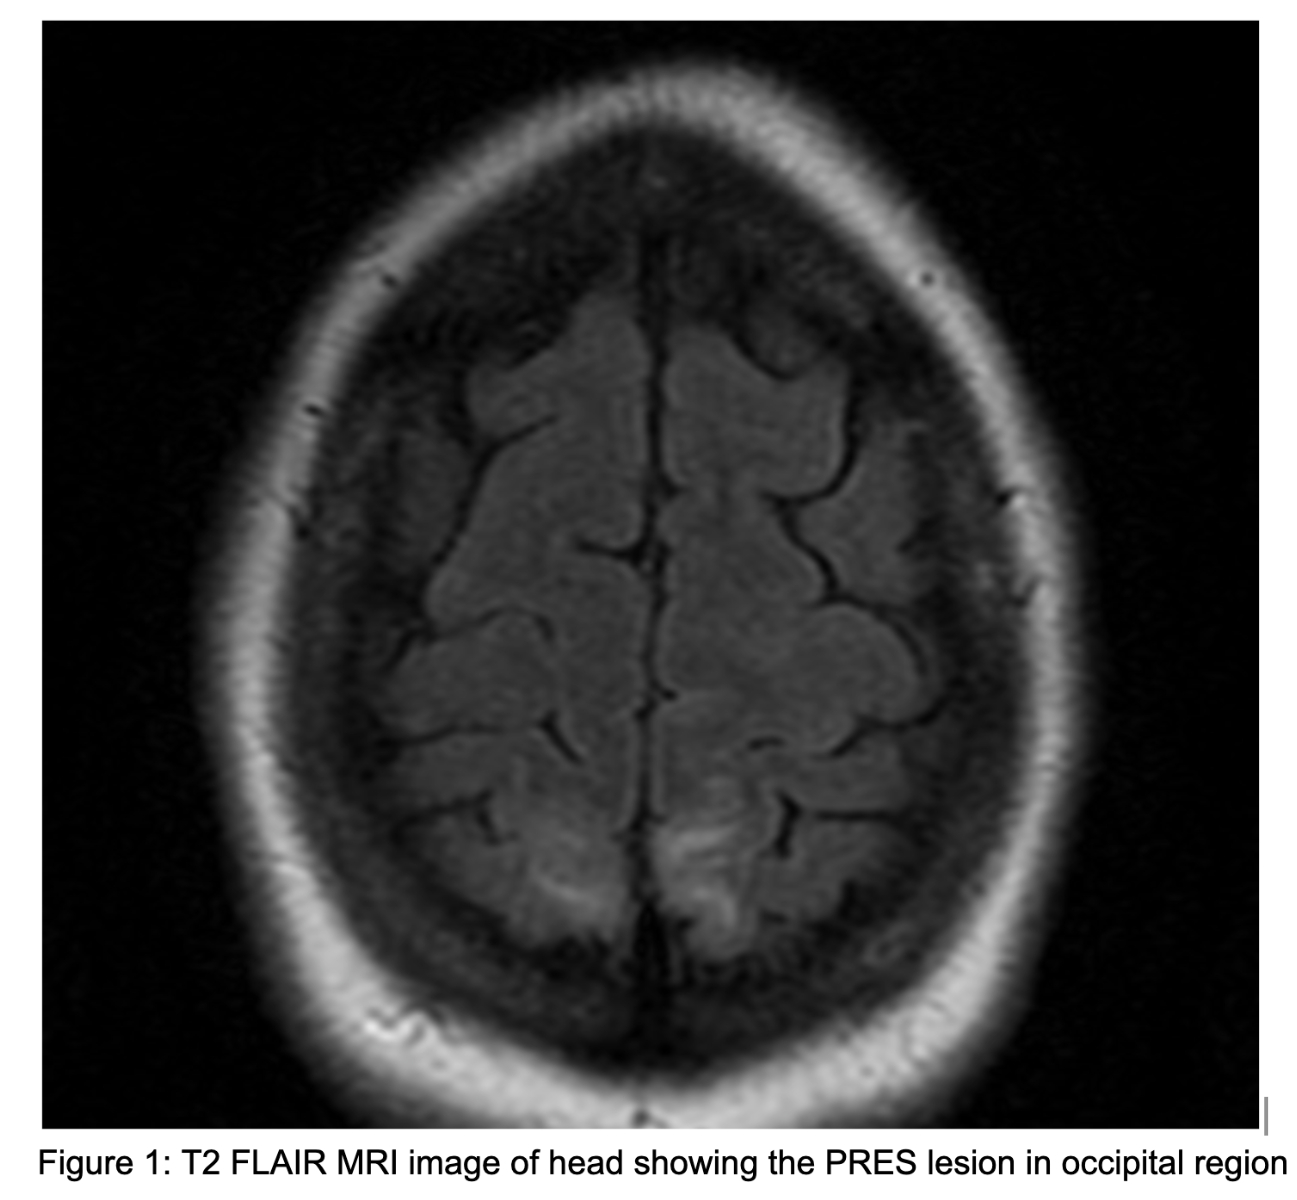

CASE PRESENTATION – A 32-year-old female with gravida 8, parity 3, abortions 4 and ectopic pregnancy 1, status post a recent normal vaginal delivery 10 days back, but with no significant past medical history, was brought to the ED after a witnessed seizure at home. She had been having a generalised headache for the past few days but could not remember details of the seizure. She complained of associated neck and back pain but denied nausea, vomiting, fever, chills, shortness of breath, chest pain, dizziness, and excessive vaginal bleeding. She had an uncomplicated vaginal delivery recently, and it was her 8th pregnancy, with the previous two being normal deliveries. The patient had seizure episodes at the hospital and mildly elevated blood pressure on admission. She was evaluated by gynaecology and was started on magnesium drip for possible eclampsia. Magnesium level was followed and maintained at 5-8 mg/dl. EEG done showed seizure potentials, but no active seizures. She got amlodipine and labetalol for elevated blood pressure. MRI brain showed subcortical white matter disease in the parieto-occipital region, with PRES. She was started on Keppra 500 mg twice daily. Her symptoms got better over a few days.

DISCUSSION – With the exact aetiology of PRES being not completely clear, one hypothesis is various risk factors causing vasospasm followed by hypoperfusion resulting in brain vasogenic edema leading to PRES. Late postpartum eclampsia with PRES is not that common. Particularly in PRES, visual impairment is common, with some patients showing decreased or asymmetric limb muscle strength, while tendon reflexes being active. The neurological symptoms, signs and radiographic changes usually disappear completely in 1-2 weeks, but if diagnosis gets delayed, then irreversible damage of neurones can occur, leading to permanent damage and also making it even life-threatening. As symptoms of pre-eclampsia does not get reported, very few get diagnosed with it at the first place, increasing the risk of onset of PRES. This particular case illustrates post vaginal delivery in females, it's important to be vigilant for maintaining normal blood pressure.